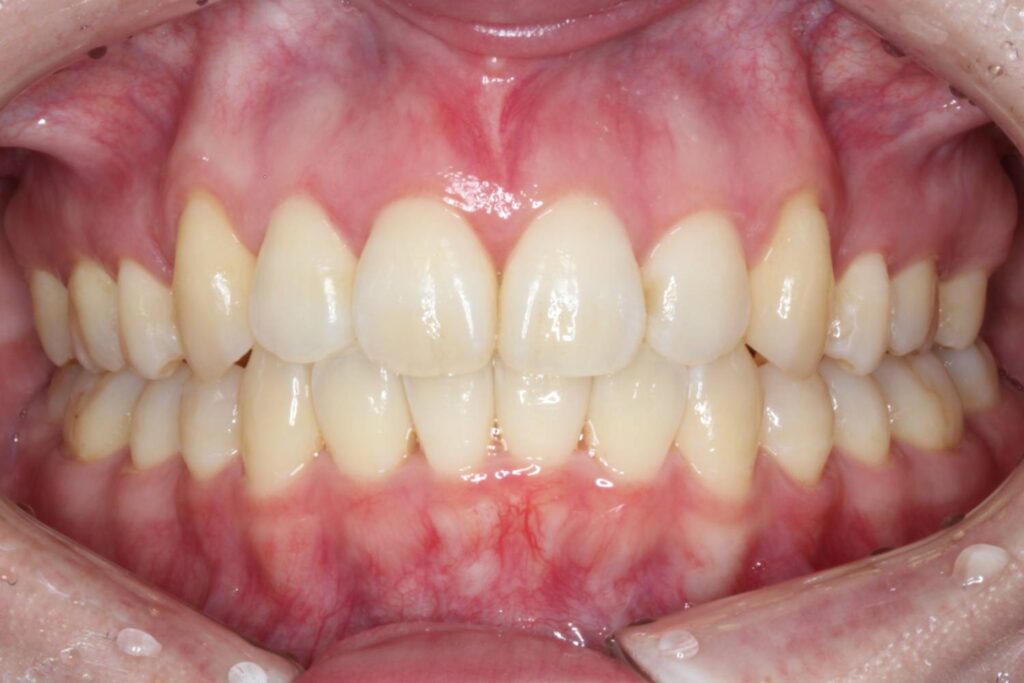

After

治療後は上顎の前歯が引っ込み、歯のがたつきも改善しています。

そうすることで、見た目だけではなく、前歯でものが噛み切りやすい機能的な歯並びが達成されました。

上顎の歯のみを抜歯していますが、噛み合わせのバランスには全く問題ありません。